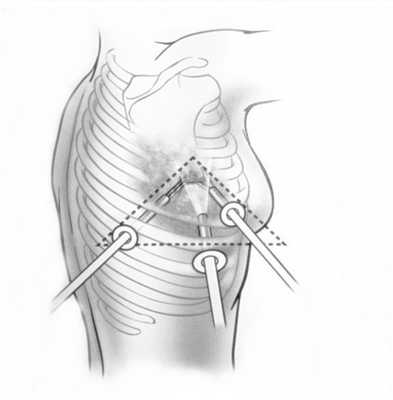

При невозможности получить образец ткани для исследования эндоскопически применяются инвазивные методы: трансторакальная биопсия, медиастиноскопия, видеоторакосокпия. Последние два метода — это серьезные операции, которые проводятся в специализированных медицинских учреждениях.

Перечисленные методы являются неинвазивными. Несмотря на их широкие диагностические возможности, ответить на все вопросы состояния органов средостения с их помощью невозможно. Например, на КТ был выявлен онкологический процесс органа средостения. Какое именно это новообразование? С помощью томографии ответить на этот вопрос затруднительно. В таких случаях может применяться инвазивный метод исследования - медиастиноскопия. Он заключается в непосредственном осмотре органов средостения с помощью специального прибора - эндоскопа. При медиастиноскопии, можно, к примеру, взять кусочек опухоли, обнаруженной при компьютерной томографии, с целью уточнения разновидности новообразования. Кроме того, можно проводить некоторые лечебные манипуляции.